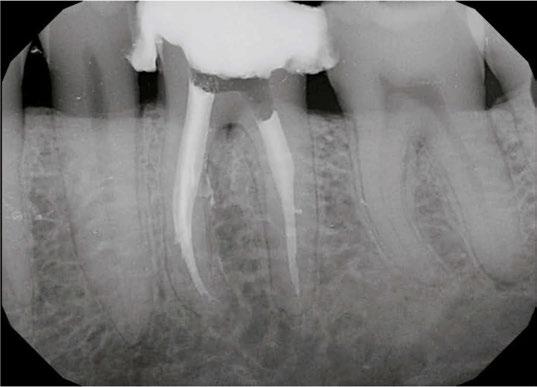

Case 1: Pre-op and diagnosis: A 68-year-old female presented with localized vestibular swelling buccal to tooth No. 30. No. 30 had been symptomatic for a few days, but the swelling started to alarm the patient and caused her to seek treatment. Upon evaluation, No. 30 was diagnosed as necrotic pulp with acute apical abscess. Two treatment options were discussed with the patient: 1) Tooth No. 30 non-surgical root canal therapy or 2) Tooth No. 30 extraction. The patient elected tooth No. 30 non-surgical root canal therapy (NSRCT). A pre-op Small FOV CBCT revealed a heavily calcified pulp chamber and calcified canals and a radix entomolaris. The CBCT revealed PARL’s at the apex of the mesial, distal, and radix entomolaris roots with the lesion extending coronally into the furcation. The patient was advised before treatment that this would be a very challenging case, and No. 30 NSRCT would be given a guarded prognosis, but she chose to proceed with No. 30 NSRCT. Treatment: No. 30 NSRCT, the patient was anesthetized with 68 mg Lidocaine with 0.034 mg EPI via IAN and 68 mg Septocaine with 0.017 mg EPI via buccal infiltration. Rubber dam isolation was utilized, and access was prepared through the PFM crown. 4 canals were located and then immediately after identification of the canal orifices, a platform was created with Soundseal, and the GentleWave Cleanflow handpiece was utilized to help break up the calcified tissue and negotiate each canal, alternating between a pathfile to slowly negotiate the coronal half of the canals and then running the GentleWave CleanFlow Procedure Instrument for 30-40 seconds to remove the accumulated debris. By alternating between files and the CleanFlow with GentleWave, all 4 canals were negotiated to length, and patency was achieved. The final working lengths were between 23 mm-24.5 mm for all 4 canals. All canals were instrumented to a Master Apical File of 20/.04 and obturated with high-flow BC Sealer. By utilizing the GentleWave and High-Flow BC Sealer, the apical delta of the distal root was cleaned, disinfected, and obturated in ways that would not have been possible with traditional endodontic therapy. Post-op: The patient was called 24 hours after treatment and reported she was pain-free, the swelling had reduced, and she was doing well.

Case 2: Pre-op and diagnosis: A 52-year-old female presented with a chief complaint of pain to hot and cold. Pulpal sensitivity testing on tooth No. 31 revealed a lingering, aching response to thermal testing. A clinical exam revealed a small crack extending from the occlusal resin over the distal marginal ridge. Probing depths around No. 31 were all <3 mm. No. 31 was diagnosed symptomatic irreversible pulpitis with symptomatic apical periodontitis. A pre-op small FOV CBCT revealed No. 31 to have a C-shaped canal morphology. Two treatment options were discussed with the patient: 1) Tooth No. 31 non-surgical root canal therapy or 2) No. 31 extraction. The patient elected No. 31 non-surgical root canal therapy (NSRCT). Treatment: No. 31 NSRCT, the patient was anesthetized with 68 mg Lidocaine with 0.034 mg EPI via IAN and 68 mg Septocaine with 0.017 mg EPI via buccal Infiltration. Rubber dam isolation was utilized, and access was prepared. Due to the C-shaped canal morphology, only two canals could be identified. Prior to placement of the SoundSeal platform, a small amount of bonding agent was placed over the crack along the distal marginal ridge and distal portion of the pulp chamber. The SoundSeal platform was securely placed to create a vacuum seal. The two canals were negotiated to achieve patency by alternating rotary instrumentation and the GentleWave CleanFlow Procedure Instrument for 30-40 seconds to thoroughly debride the internal anatomy. The mesial canal was instrumented to a Master Apical File of 20/.04, while the distal canal to a 25/.04 Master Apical File. Due to the larger and more irregular canal morphology of the distal canal, various-sized gutta-percha cones were used to gauge the size to be used for obturation. The mesial canal was obturated with a Sealer-based obturation method with High Flow BC Sealer and a single 20/.04 master cone. The distal canal was obturated with High Flow BC Sealer and Warm Vertical Compaction. With the aid of the GentleWave and the CleanFlow Procedure Instrument, the C-Shaped canal anatomy was more deeply cleaned, pulp tissue more thoroughly removed, and this case was completed in a single visit which would have been much more difficult to accomplish with traditional endodontic therapy.

10 Endodontic Practice US Volume 17 Number 1 COVER STORY